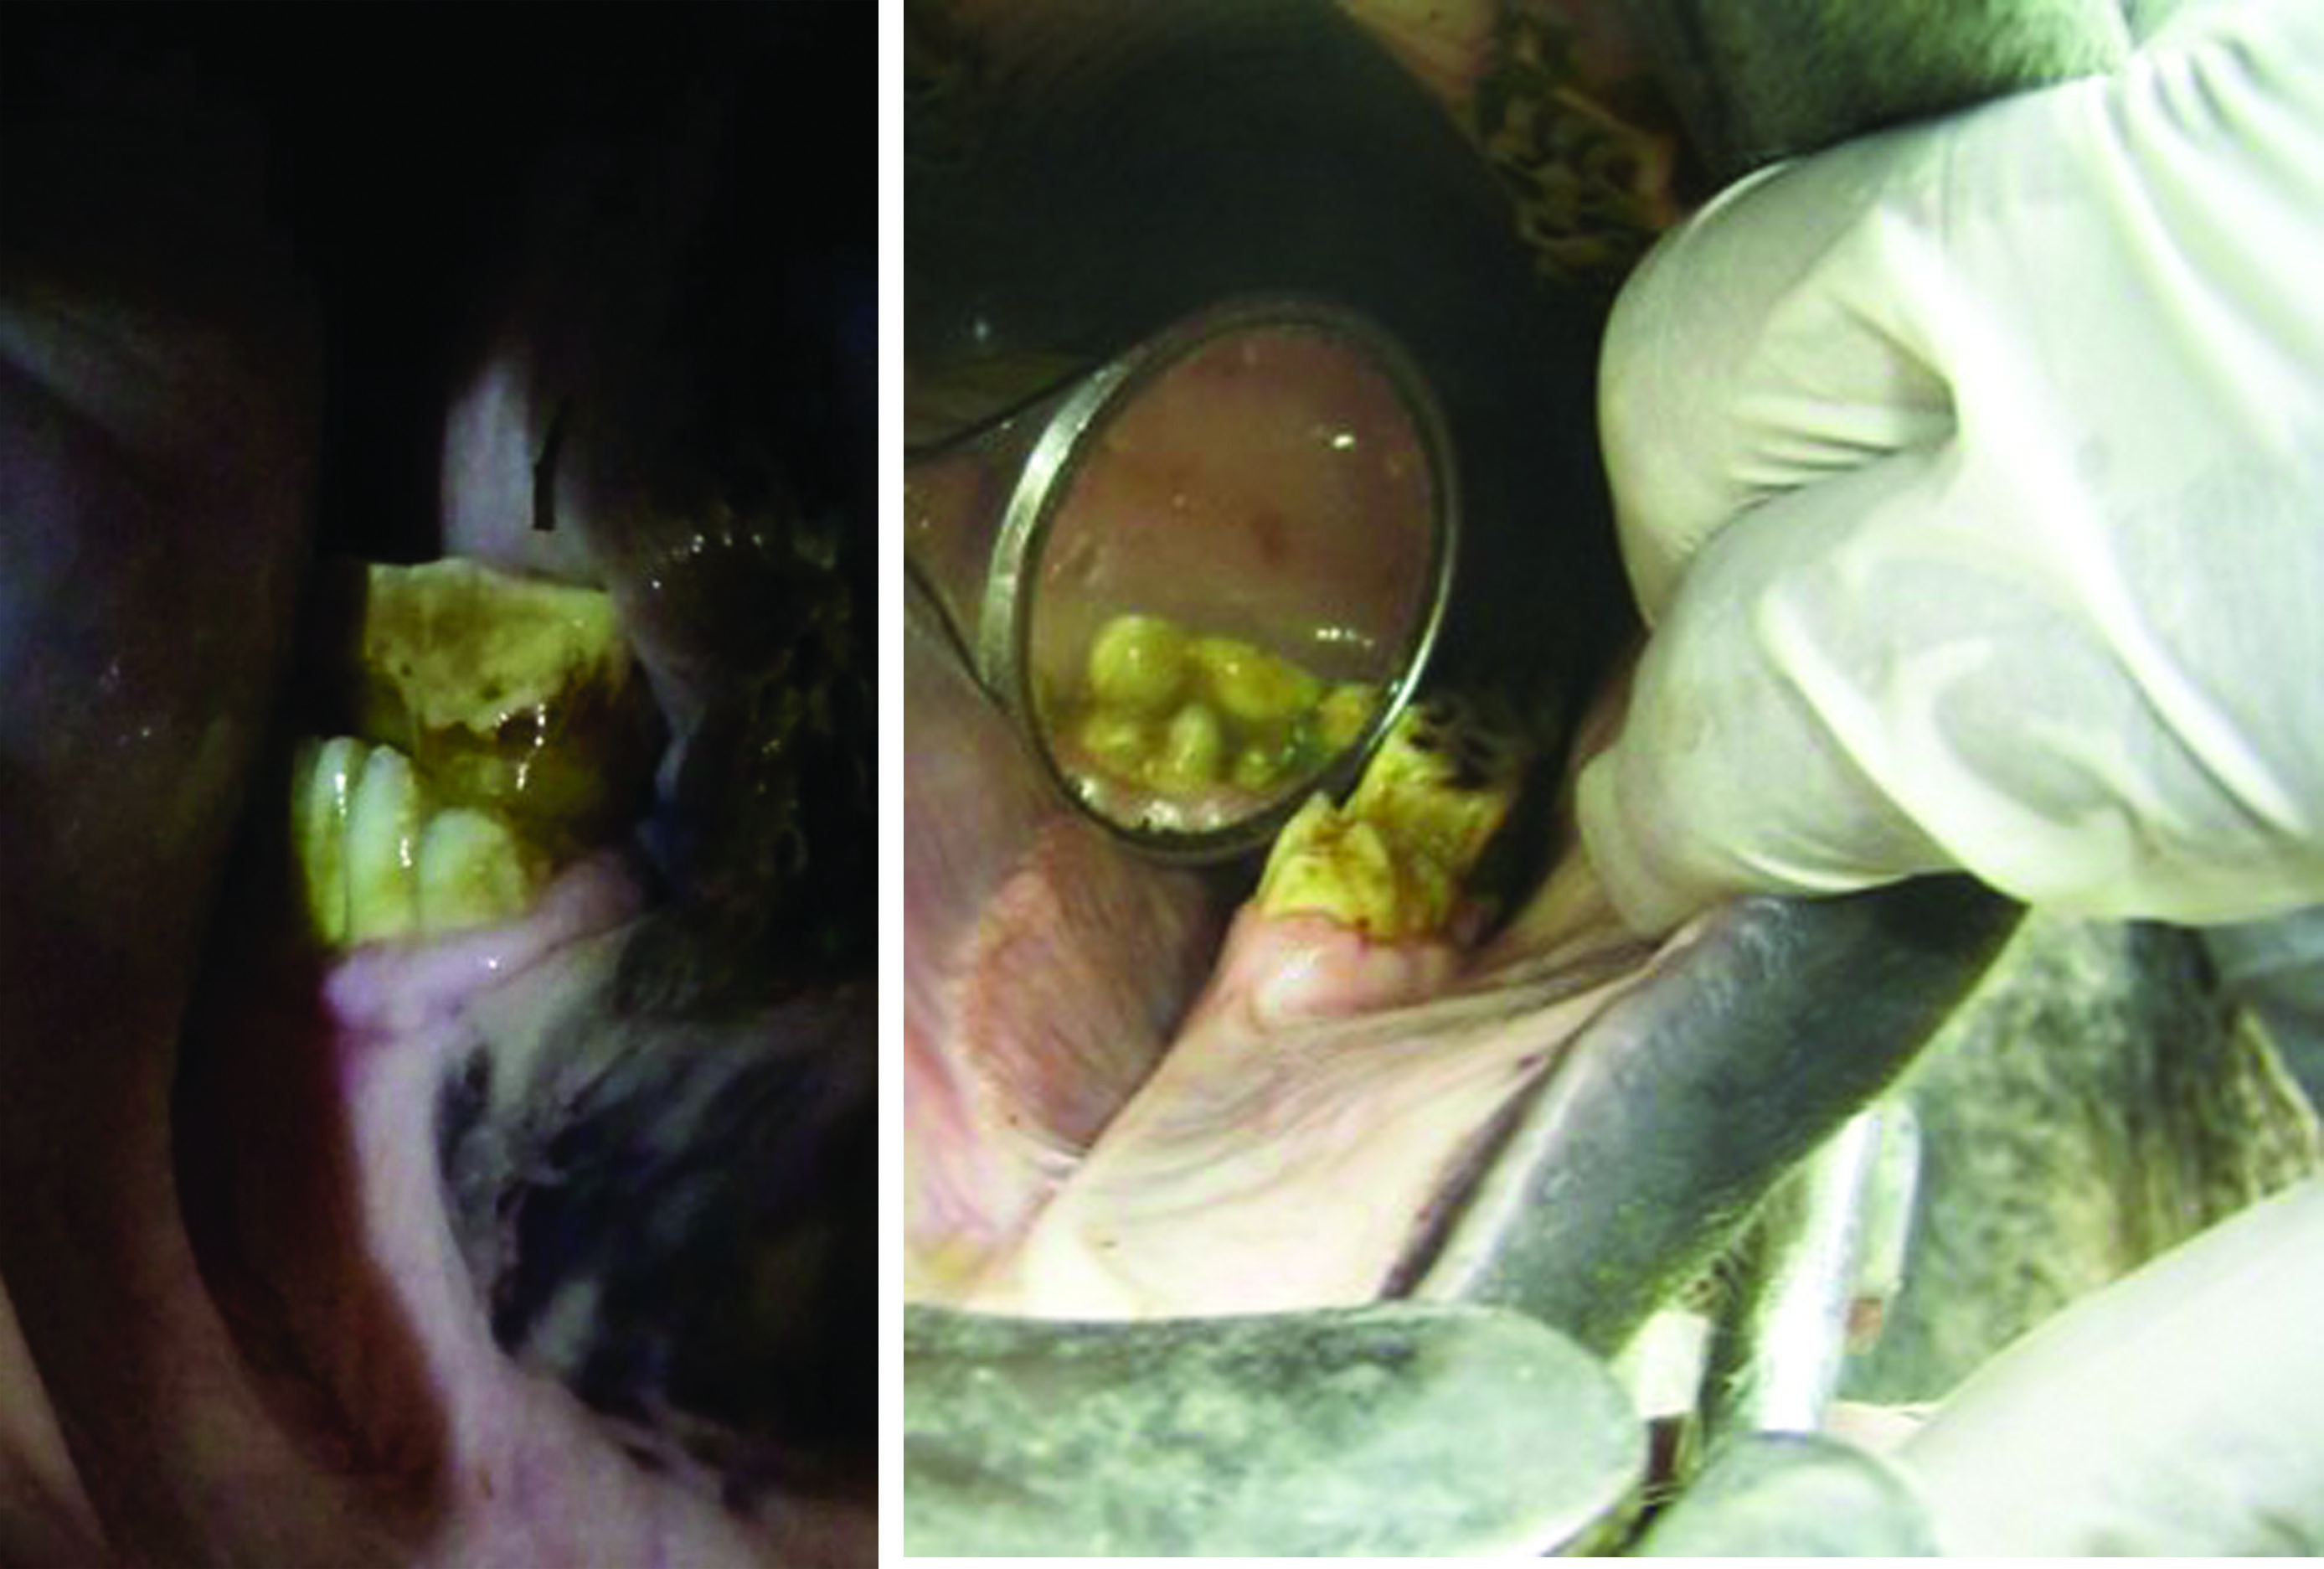

All equine teeth can become diseased due to trauma, abnormal wear, diet and age.

Caries can affect both the outer and inner parts of the tooth which are termed ‘Peripheral’ and ‘Infundibular’ retrospectively. Both types of caries are are graded on their severity which takes into account depth of cavity and dental tissue involvement.

Caries can be tricky to identify and grade correctly which is why a good headlight is fundamental during a dental examination. Mirrors and probes are then used to further investigate any problematic areas.

Caries affecting the inner aspect of the tooth known as infundibular caries can be treated by filling if caught early enough. Filling halts the degenerative nature of the disease and can save the tooth from fracturing in years to come. Peripheral caries can be more difficult to treat but is associated with high sugar diets, often a simply dietary adjustment can make all the difference.